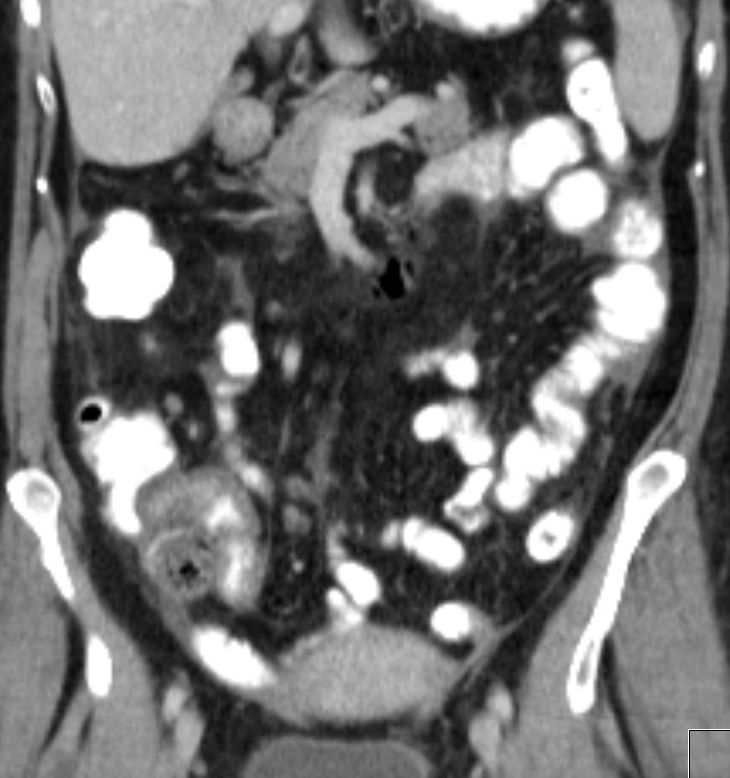

| Peritoneale Metastasen | 74-jährige Frau mit endometrioidem und klarzelligen

Karzinom des Uterus. Zeichen der peritonealen Aussaat.![]()  |